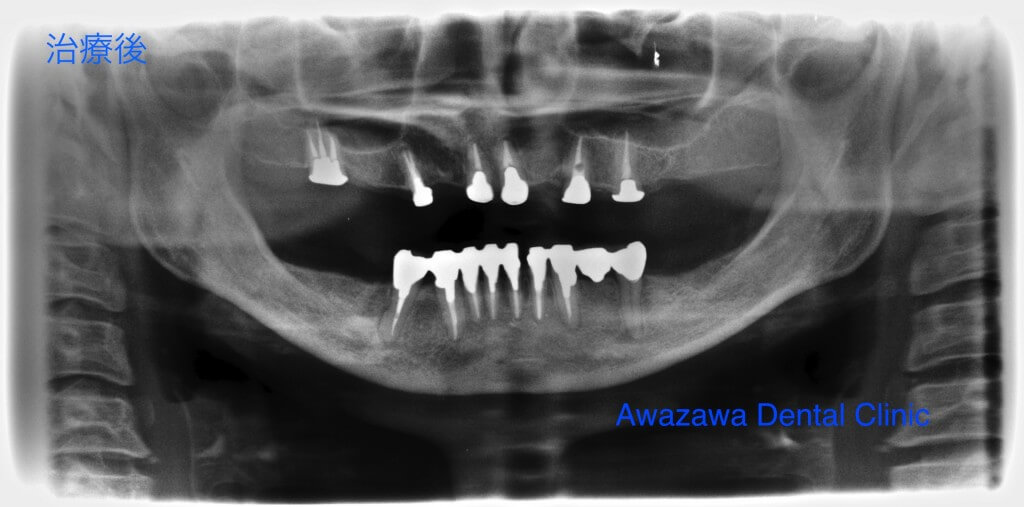

歯周病により咬合崩壊をきたした症例です。上顎は歯周病の治療の後に歯周補綴を行い、下顎はインプラントによるフルブリッジにより安定した咬合を再建した症例です。